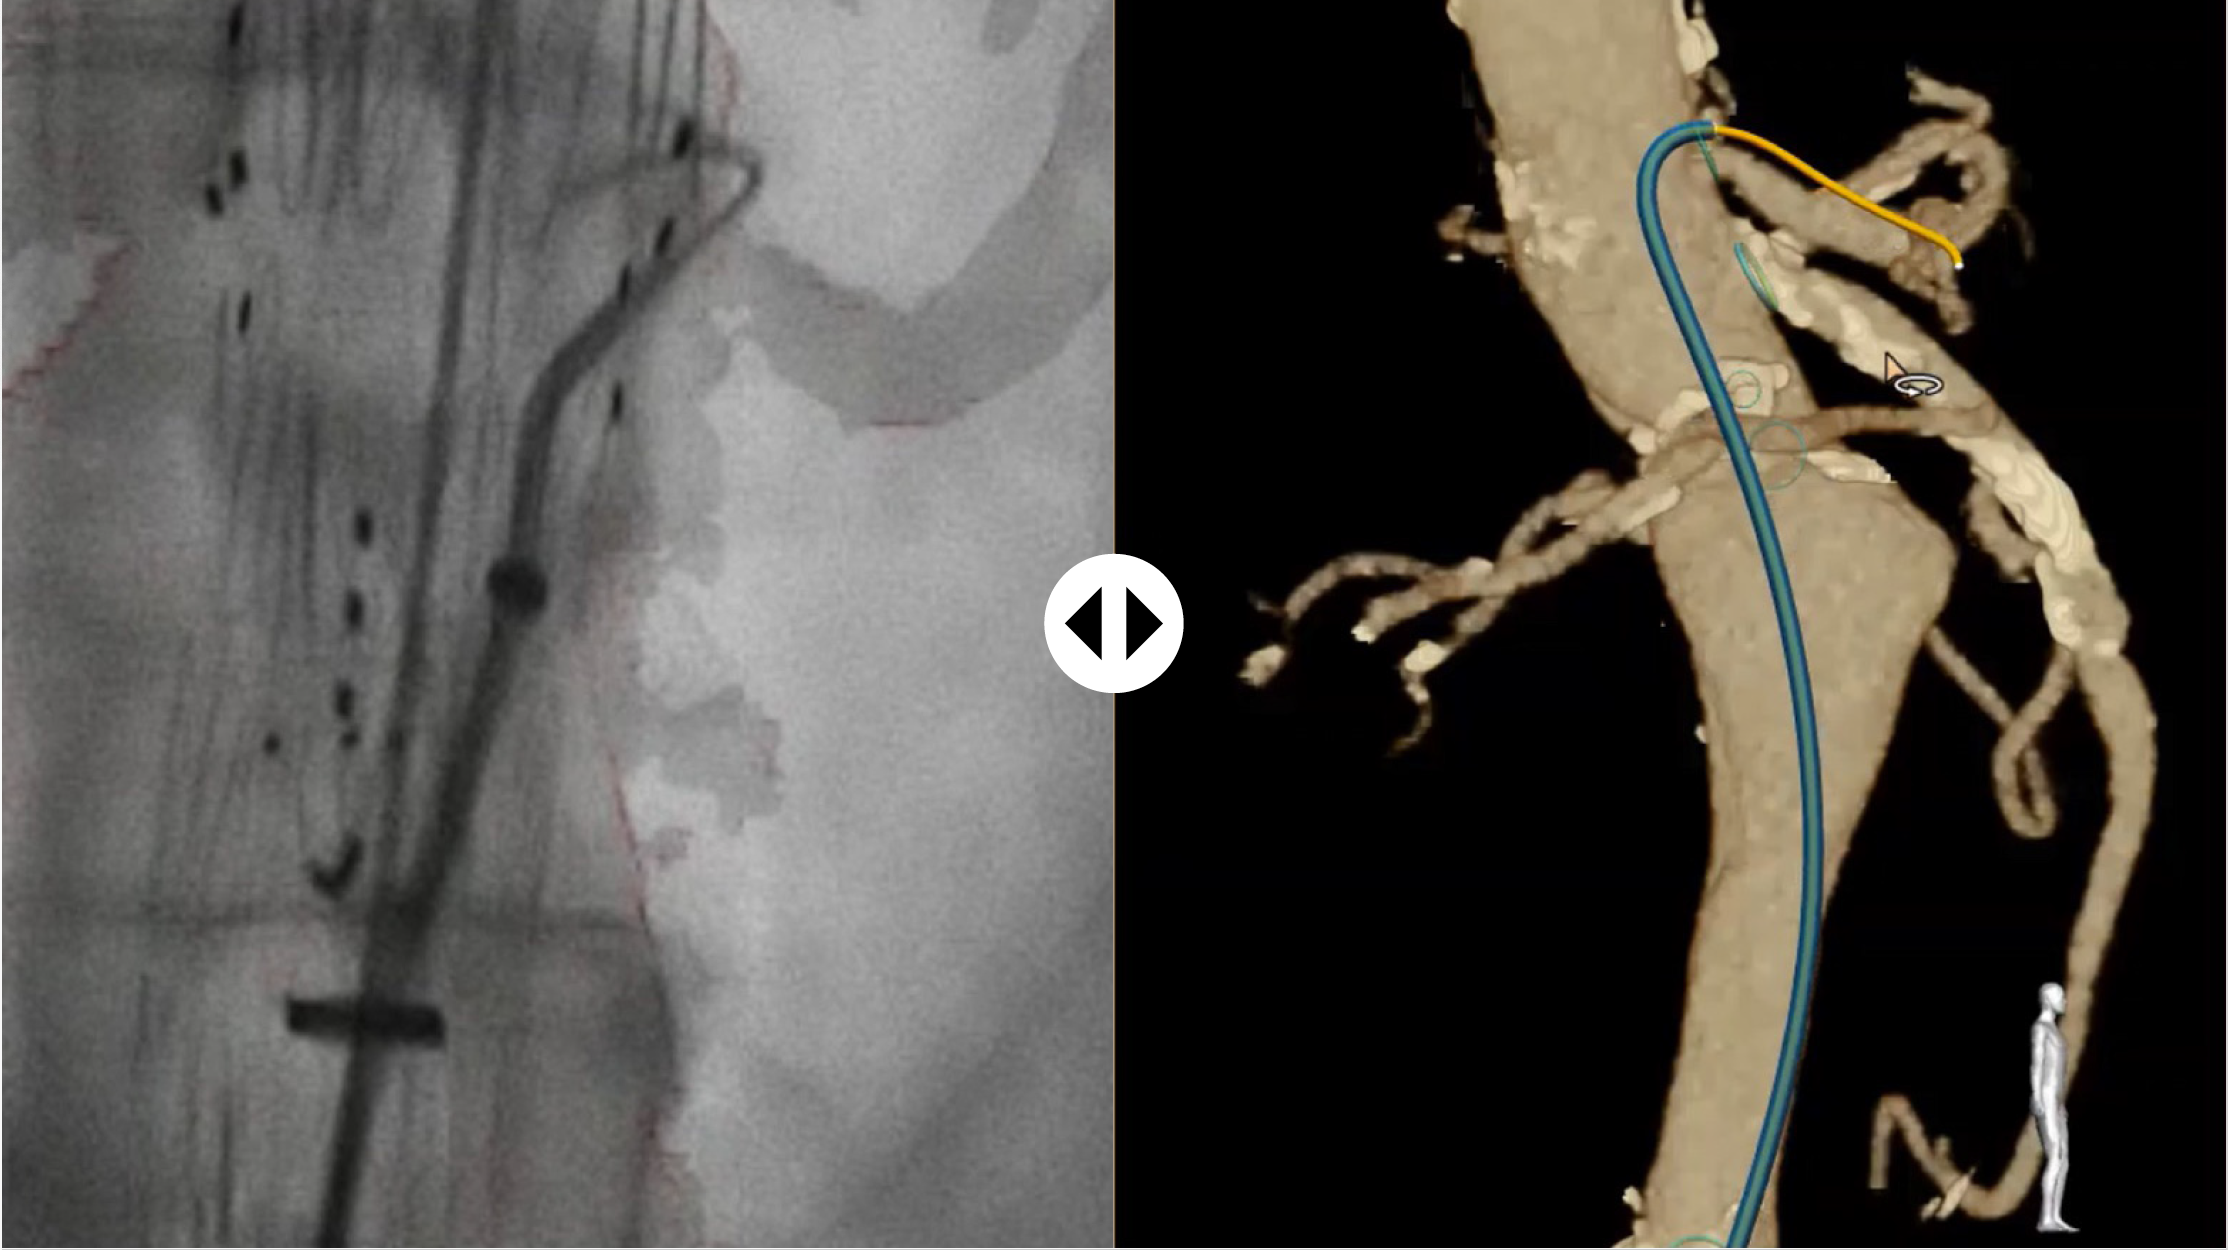

LumiGuide uses light reflected along an optical fiber inside a guidewire to generate 3D, high-resolution, color images of devices, including off-the-shelf catheters, inside a patient’s body in real time, from any angle and in multiple views. It means that physicians know which direction their device is facing and can see where they need to go. This navigation can be done all without X-ray.

"If we can see more, we can proceed more quickly and more confidently," said Dr. Atul Gupta, Chief Medical Officer for Image Guided Therapy and Precision Diagnosis at Philips and practicing interventional radiologist. “In effect, LumiGuide is a 3D human GPS powered by light.”